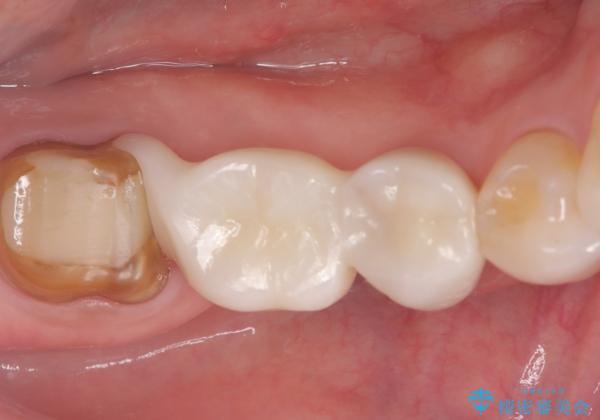

- 主訴:右下のセラミックのブリッジが何度も同じところで折れて壊れてしまう。

対合歯との咬合関係において、右下7番目と6番目の被せものの連結部がたわみやすい環境にあったため、ブリッジの新製ではなくインプラント治療を行いすべての歯を単冠仕上げとすることにしました。

何度も右下6、7間でブリッジが折れてしまうとのことでした。対合歯とブリッジの連結部が強く当たりたわみやすい状態でした。破折しずらい金属を使用したブリッジの選択もありましたが、支台歯(右下7)が失活歯場合、破折リスクが高く、破折してしまった場合にまたブリッジを外しての再治療になってしまう可能性を説明したところ、全て単冠仕上げとできるインプラント治療を希望されました。

右下5番のクラウンは、ブリッジを切断しそのまま使用していただいています。